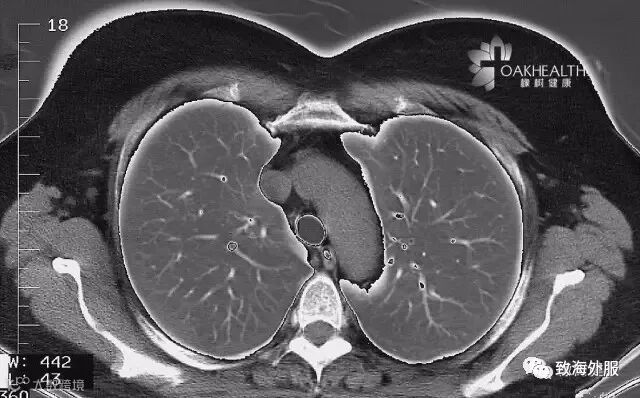

胸部CT

相比胸部X光射线,胸部CT则更清晰,准确性更好,特别是对于肺部微小结节、肿块。主要用于发现早期肺癌、肺部纵膈肿瘤、肺结核、肺炎、肺气肿、气胸和支气管炎等疾病。

•适用人群:吸烟人群,长期在空气不良环境下工作和生活的人群,40岁以后健康人群。

•推荐周期:建议每年检查1次。